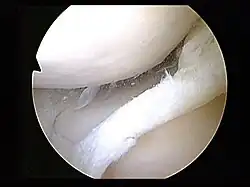

Surgery

Arthroscopy is a surgical technique in which a joint is operated on using an endoscopic camera as opposed to open surgery on the joint. The meniscus can either be repaired or completely removed.[20] Surgery is not appropriate for a degenerative meniscus tear, absent locking or catching of the knee, recurrent effusion or persistent pain.[25] Evidence suggests that it is no better than conservative management in those with and without osteoarthritis.[31][32] Surgery appears to offer no benefit to adults who have mild arthritis.[32]

If the injury is isolated, then the knee would be relatively stable. However, if an injury such as an anterior cruciate ligament injury (torn ACL) is coupled with a torn meniscus, then an arthroscopy is recommended. A meniscal repair has a higher success rate given an adequate blood supply to the peripheral rim.[36] The interior of the meniscus is avascular, but the blood supply can penetrate up to about 6 millimetres (0.24 in). Therefore, meniscus tears that occur near the peripheral rim are able to heal after a meniscal repair.[1] One study found that repair is better than removal (meniscectomy). The amount of rehabilitation time required for a repair is longer, but removing the meniscus can induce osteoarthritis. Meniscectomy rehab requires four to six weeks. Repair requires four to six months. If conservative treatment is ineffective, surgical intervention may be required. Younger patients are typically more resilient and respond well to this treatment, while older, more sedentary patients do not have a favorable outcome after a repair.[37]